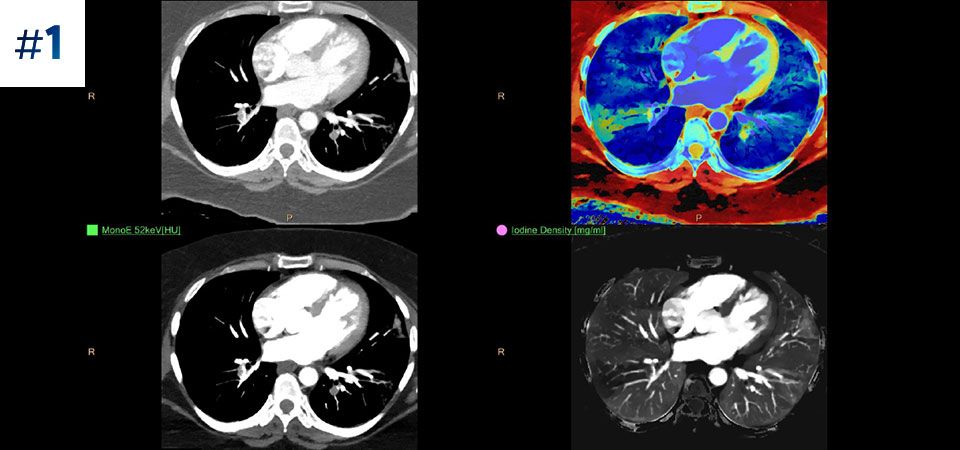

With detector-based spectral, you acquire multiple layers of data—conventional and spectral—within a single exposure and without special scan modes for improved tissue characterization and visualization.

Scan as usual A single scan for fast, low-dose conventional and spectral data for every patient, every time.

Always available 100% spectral, 100% of the time for results that are always available on-demand, even retrospectively.

Reduced follow-up exams Improved tissue characterization and visualization may reduce the need for follow-up scanning for sub-optimal exams and incidental findings.